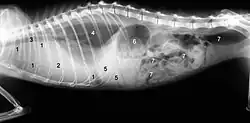

Die klassische „feuchte Form“ äußert sich in Flüssigkeitsansammlungen in der Bauchhöhle (Bauchwassersucht, Aszites) oder in der Brusthöhle (Pleuraerguss). Die Flüssigkeitsansammlungen in der Bauchhöhle können als Umfangsvermehrung mit Fluktuation meist klinisch diagnostiziert werden. Flüssigkeitsansammlungen in der Brusthöhle können zu schwerer Atemnot führen. Eine Punktion liefert eine gelbliche, fadenziehende, viskose Flüssigkeit. Die Tatsache, dass es sich hierbei um ein proteinreiches Exsudat handelt, welches in seiner Erscheinungsform recht typisch ist, ist ein wesentliches diagnostisches Kriterium.